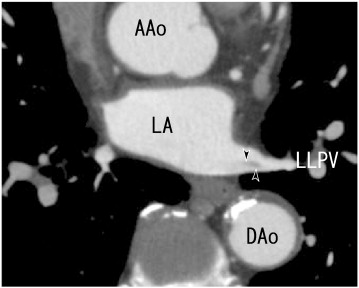

64-MDCT axial images showed thrombi in the left lower pulmonary vein (LLPV) ...

Fig. 3.

64-MDCT axial images showed thrombi in the left lower pulmonary vein (LLPV) (arrowheads). AAo: ascending aorta, DAo: descending aorta, LA: left atrium, and LLPV: left lower pulmonary vein.